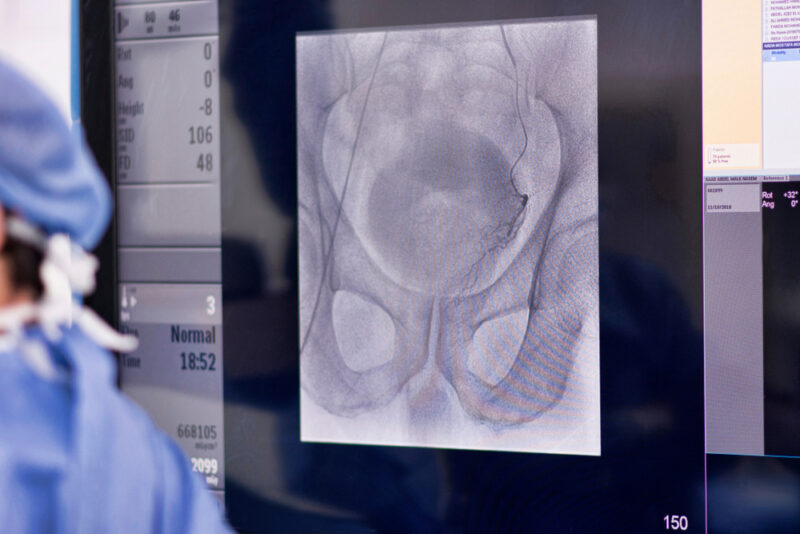

MRI Fusion Biopsy: A Modern Tool for Prostate Evaluation

Advancements in prostate imaging have revolutionized the way physicians detect and evaluate prostate abnormalities. One such advancement, MRI fusion biopsy, has become an important tool